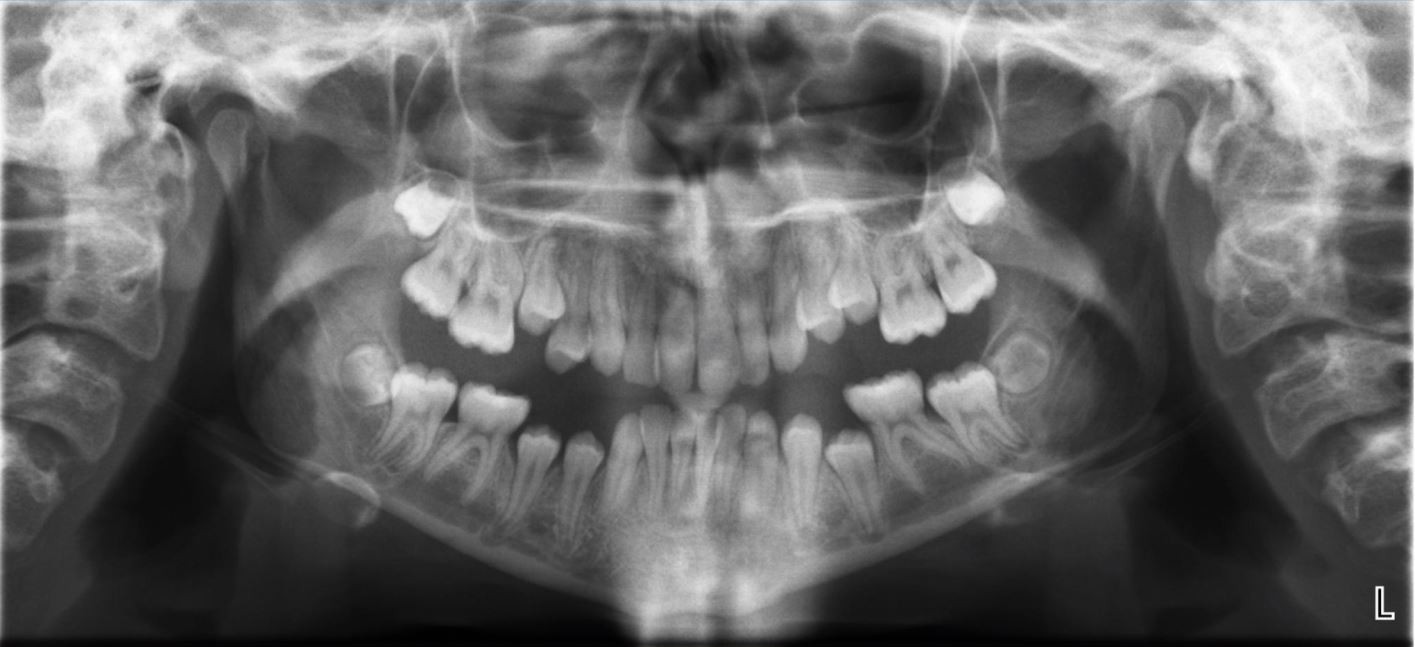

The surgeon discussed the risk of paresthesia with her during the consultation and sure enough after the removal of her lower wisdom teeth she had lost sensation in the middle of her lower lip and her chin. The inferior alveolar nerve is a sensory nerve and this is the nerve that was inflamed from the procedure. While your wisdom teeth are being removed this nerve can become damaged or impinged causing paresthesia or numbness in the area.

Your lips and chin are typically affected by this numbness and sometimes the cheek area is also involved. IAN paresthesia may occur after various dental procedures such as simple anesthetic injections surgical procedures and endodontic treatment and is reported to range from 035 to 84. The altered sensation usually follows immediately after the procedure and reports of late onset of nerve involvement are rare.

A follow-up visit may be necessary as lingering numbness after an oral procedure could indicate nerve damage or. The removal of mandibular third molars frequently results in associated morbidities the most concern is about paresthesia or permanent numbness from nerve damage. I have also frequently seen patients with TMJ disorders TMD such as joint locking clicking or pain after removal of wisdom teeth.